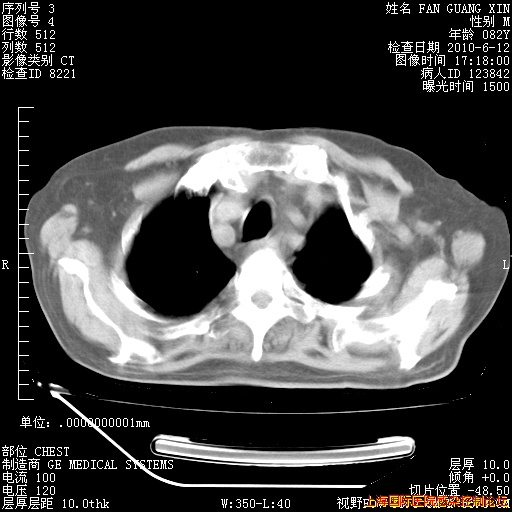

6月12日纵膈窗